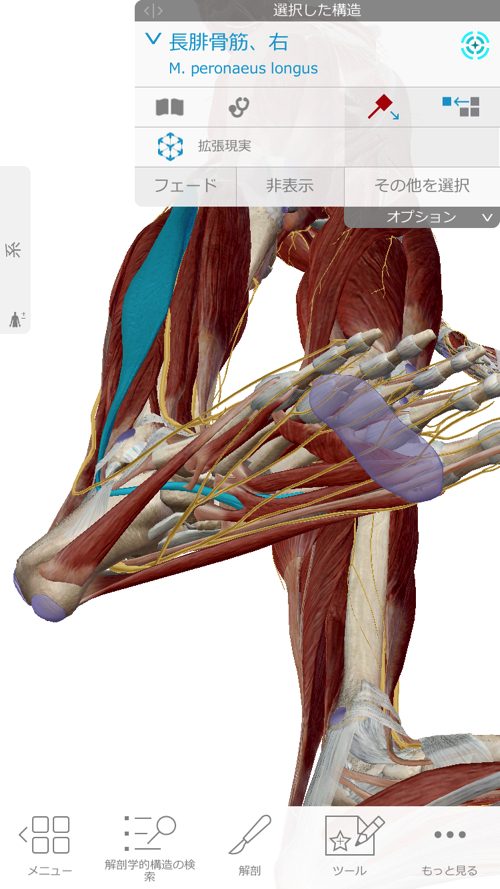

長腓骨筋は足裏からクルブシを通って膝の方へ繋がっていきます。

腓骨筋の先には親指を動かす短母趾屈筋

同じく趾に影響の大きい母趾内転筋にも連携しています。

長腓骨筋は膝・足首・足裏・足の指に全て影響するのがお分かり頂けたと思いますが

足だけ、膝だけ・腰だけと部分部分で切り取った見方では、脚全体の硬直や捩れ、微妙なズレなどは絶対に分からないし、レントゲンやMRIには、この長腓骨筋などの硬直やヨジレは写らないのです。